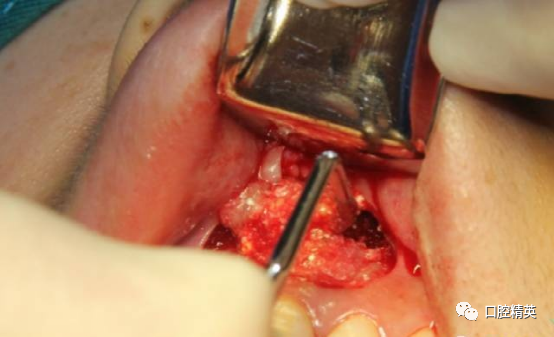

BIO-OSS骨粉混合PRF填补骨缺损。

上方覆盖PRF膜3-5份。完全覆盖骨缺损,减张缝合。

唇系带处理后做第一缝合位点,梯形边角区做第二第三缝合位点。

缝合完成。塞治剂塞治,局部加压。